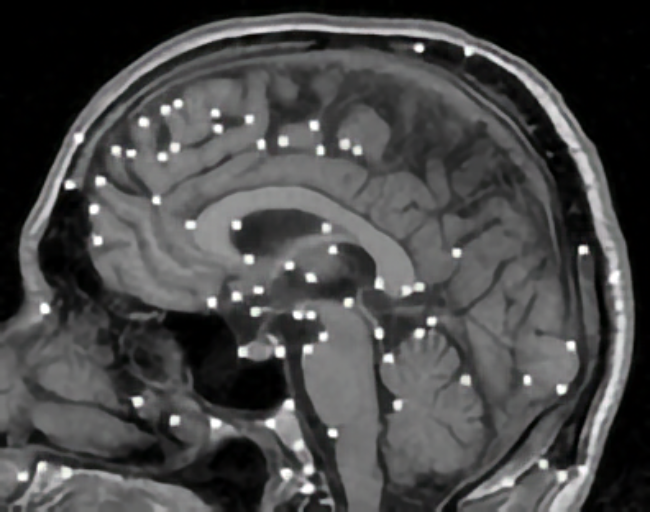

Elastic registration of 2D and 3D multimodal medical images (MR, CT) for diagnosis, surgical planning, and therapy. Spline-based registration approaches using landmarks, intensity information, and landmark localization uncertainties.

Localization of 3D anatomical point landmarks in 3D tomographic images. Development of differential and model-based approaches.